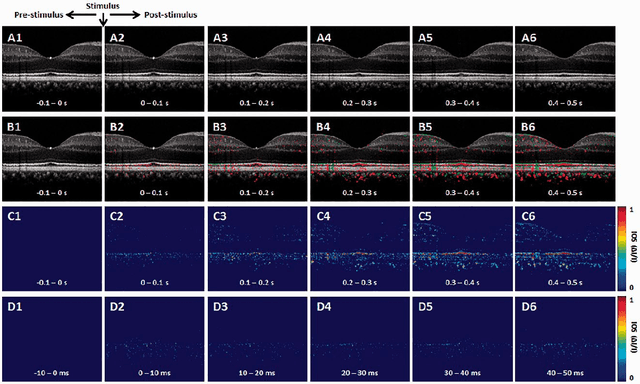

Abstract:Intrinsic optical signal (IOS) imaging of the retina, also termed as optoretinography (ORG), promises a noninvasive method for objective assessment of retinal function. By providing unparalleled capability to differentiate individual layers of the retina, functional optical coherence tomography (OCT) has been actively investigated for intrinsic signal ORG measurements. However, clinical deployment of functional OCT for quantitative ORG is still challenging due to the lack of a standardized imaging protocol and the complication of IOS sources and mechanisms. This article aims to summarize recent developments of functional OCT for ORG measurement, OCT intensity- and phase-based IOS processing. Technical challenges and perspectives of quantitative IOS analysis and ORG interpretations are discussed.